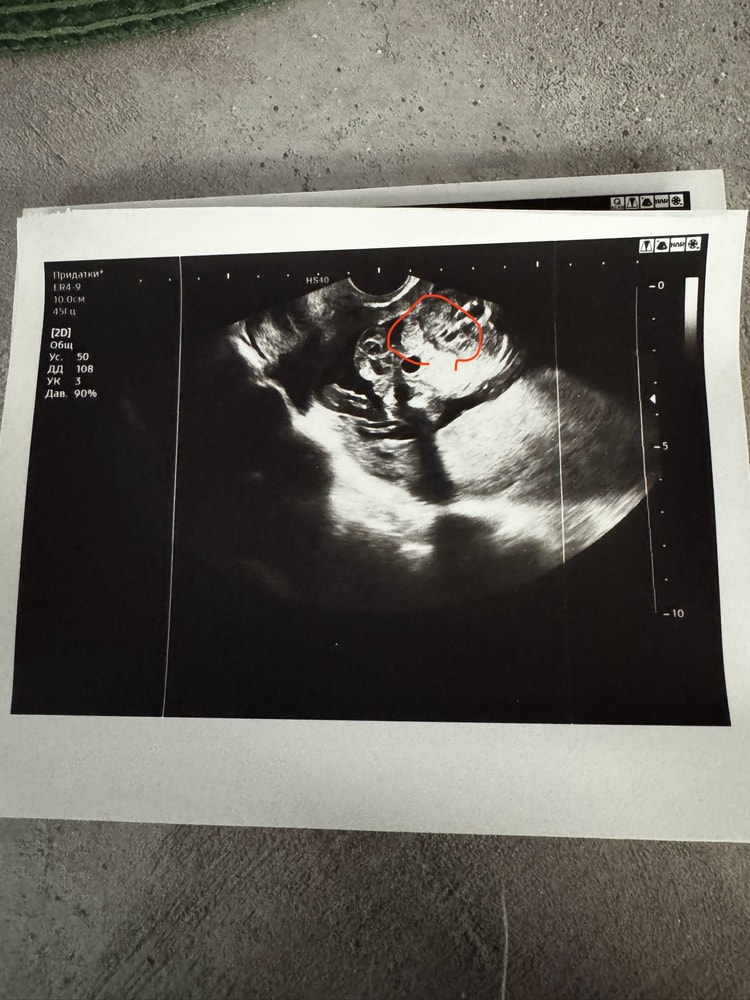

Малышка или малыш 👶

Пол малышаходили на 16й неделе на узи сказали пацан , пришли потом на узи через 2 недели (у мужа день рождения был хотели точно узнать и гендер пати сделать) сказали уже девочка Первое фото 16 недель , второе 18 и вид снизу на пуповине сидит